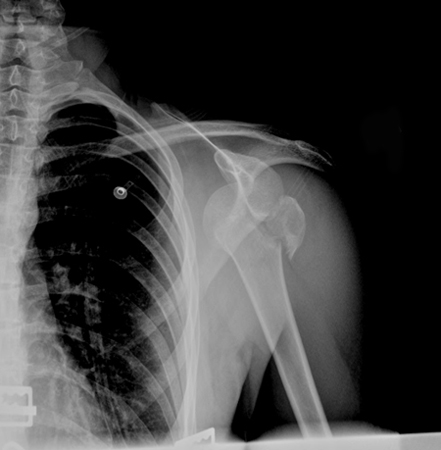

Radiografia com incidência anteroposterior de ombro mostrando luxação anteroinferior

Acervo pessoal do Dr. Paul Novakovich